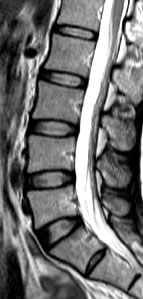

Low back pain affects every population worldwide, and is a leading cause of ill-health and sick leave in the working population of Hong Kong. One of the major causes of low back pain is degeneration of the joints of the spine, known as the intervertebral discs. A cohort study conducted by the Department of Orthopaedics & Traumatology at The University of Hong Kong Li Ka Shing Faculty of Medicine reveals that being obese in adulthood doubles the likelihood of having disc degeneration and developing more severe forms of the condition than those of normal weight. These findings are of public health concern and were published in the latest issue of the authoritative journal Arthritis and Rheumatism.

The current study was a cross-sectional assessment of adults from this cohort who were 21 years of age and older. A total of 2,599 individuals were assessed with magnetic resonance imaging (MRI). Amongst them, 27% (n=709) did not have disc degeneration while 73% (n=1,890) had. Of the subjects who have disc degeneration, 7% were underweight, 48% were in the normal weight range, 36% were overweight, and 9% were obese. Overweight and obese individuals were also found to have a greater extent and severity of disc degeneration in comparison to those individuals of normal weight or underweight.